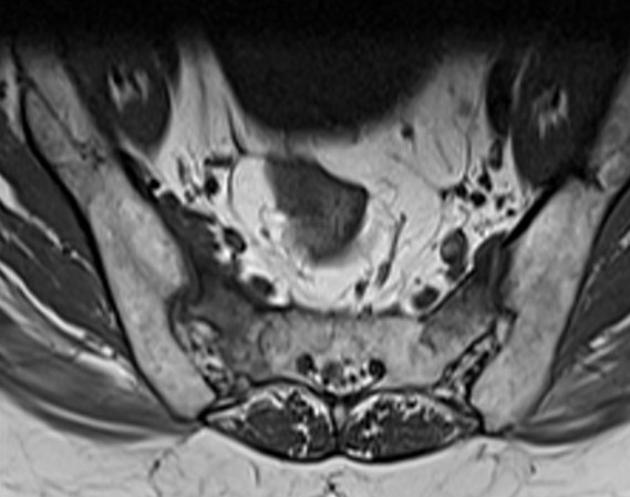

磁共振检查:

T1

影像表现

2、单侧或双侧骶骨翼骨皮质断裂,见迂曲纵行骨折线,大致与骶髂关节平行(双侧多见);

3、骶骨体部看见骨折线

4、冠状位上述骨折形成 “H”型 ,故有人称东风本田征(为了方便记忆)

5、骨折线一般较为模糊,看见看到骨质硬化;

6、磁共振上可以发现骨折线周边明显的骨髓水肿,增强扫描明显强化

磁共振影像表现